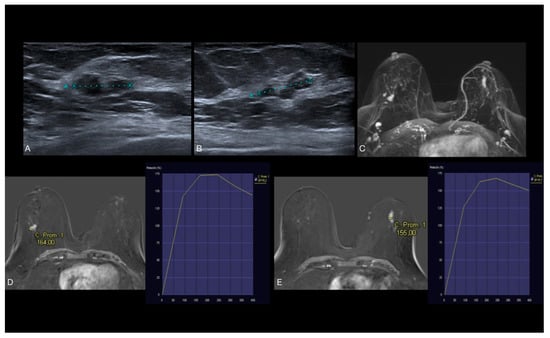

3.3. US Features

3.4. MRI Features